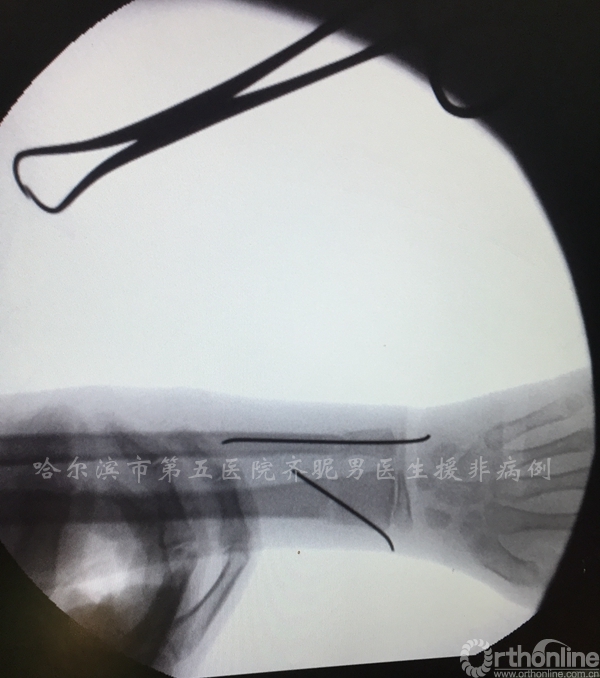

由于这里每家每户孩子都多,所以大多数都是散养,儿童骨折非常常见,比如肘关节骨折——

前臂骨折等——

随着中国派出医疗队医生的技术水平越来越高,当地的医疗技术也得到了提升,对于儿童的骨折大多数采取的都是闭合复位微创内固定技术,这一点是跟国际接轨的。